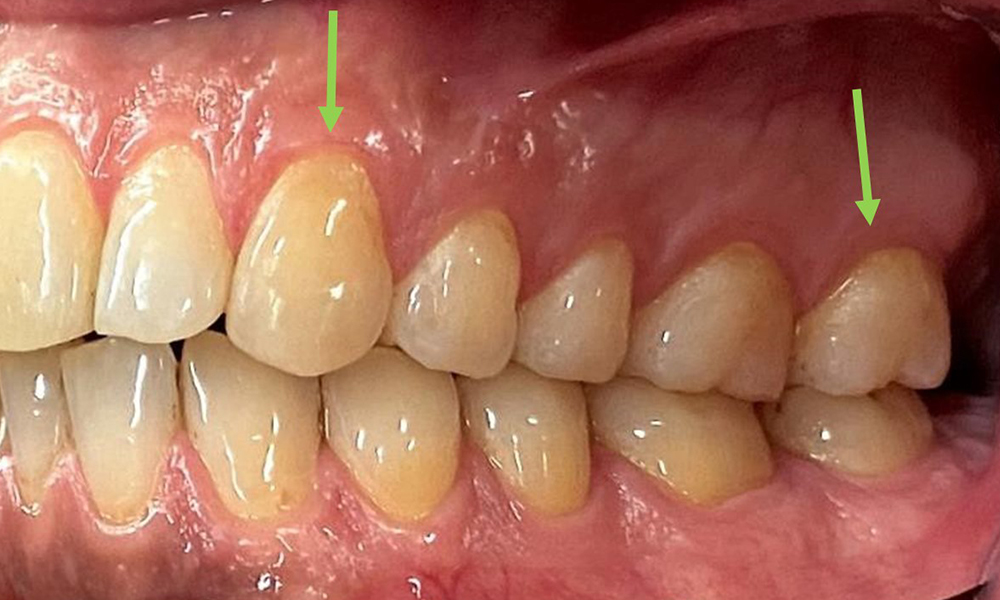

Extraoral sind keine pathologischen Befunde festzustellen, intraoral zeigen sich bei der Frontalansicht im Bereich der keratinisierten Gingiva und am Übergang zur beweglichen Schleimhaut bräunlicheVerfärbungen (Abb. 2), welche auf den Nikotingenuss zurückzuführen sind. Am Gaumenbereich zeigen sich insbesondere im Bereich Oberkiefermolaren palatinal weißliche Schleimhautveränderungen, die ein Hinweis auf einen erhöhten Verhornungsgrad sind und ebenso auf den Nikotingenuss zurückzuführen sind. Die Zunge ist mit einem weiß-bräunlichen abwischbaren Belag versehen.